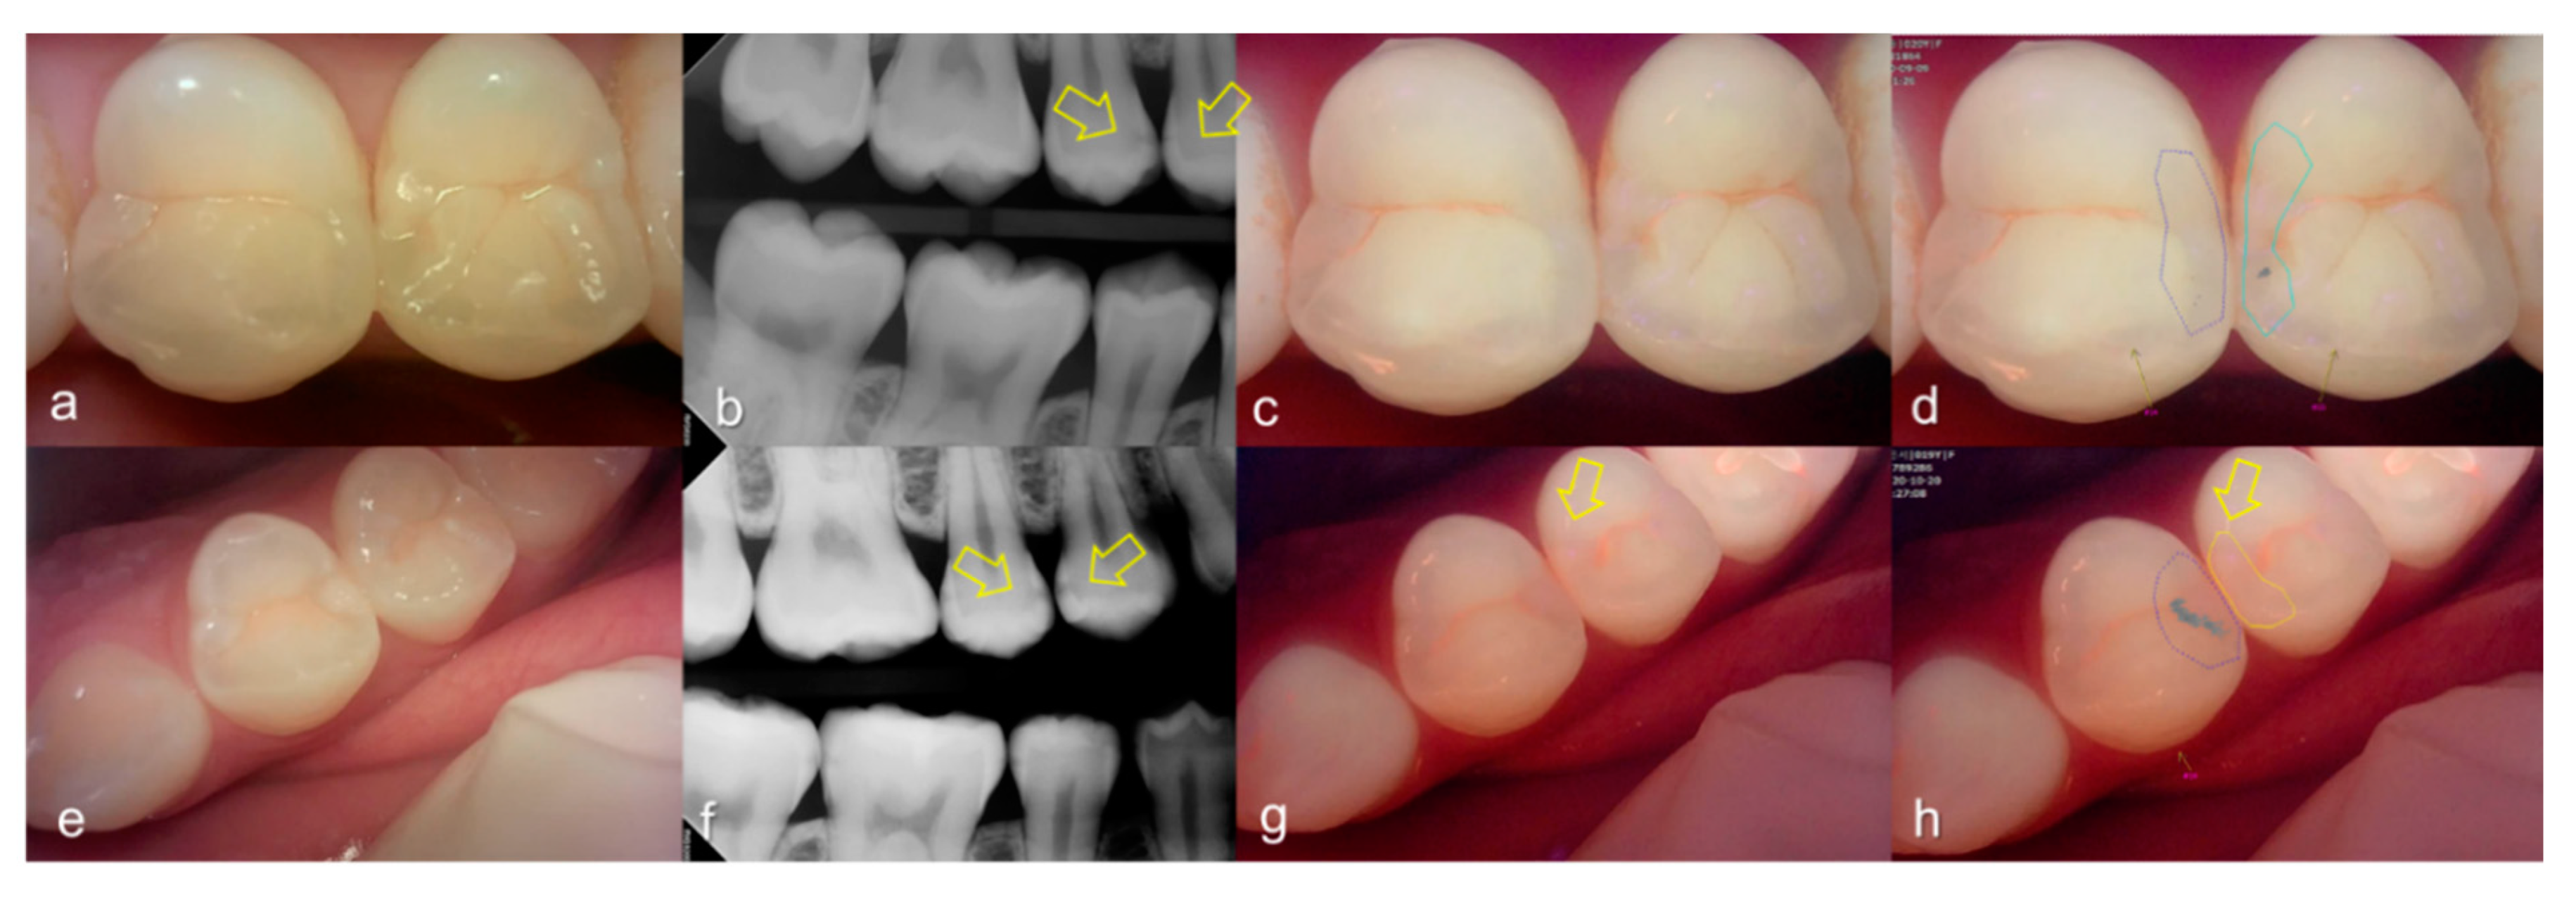

Figure 8.

Proximal dental caries: (a–d) QLF caries score 0 (no fluorescence loss and no red fluorescence increase in occlusal surface (distal side)) and radiographic caries score 4 (radiolucency in the pulpal 1/3 of the dentine) on #26; (e–h) QLF caries score 2 (fluorescence loss and red fluorescence glow extending around occlusal surface (distal side)) and radiographic caries score 4 (radiolucency in the pulpal 1/3 of the dentine) on #25 (a,e): white-light image of QLF; (b,f): fluorescence image of QLF; (c,g): bitewing radiograph; (d,h): analyzed QLF image using QA2 software.

3.3. Crack

The values of the QLF parameter according to the value classified based on the QLF criteria were significantly different (Table 2). The cut-off value of |ΔFmax| and ΔRmax for determining a crack (QLF criteria scores 0 and 1 vs. 2) was 20.80 and 39.00, respectively. In addition, the AUROC of QLF parameters were similar (0.83, 0.82) (Table 3). Representative images of QLF and bitewing radiograph of dental cracks are shown in Figure 9 and Figure 10.

Figure 9.

Cracks: (a) white-light image of QLF, visual examination score 0 (No detectable crack line) on #15; (b) fluorescence image of QLF, QLF caries score 1 (fluorescence loss and red fluorescence present as a line in a crack site) on #15.

Figure 10.

Cracks: (a–d) QLF caries score 2 (fluorescence loss and red fluorescence glow extending around crack site) and visual examination score 0 (no detectable crack line) on #25; (e–h) QLF caries score 2 (fluorescence loss and red fluorescence glow extending around a crack site) and visual examination score 1 (ambiguous detectable crack line) on #17 (arrow 1), QLF caries score 1 (fluorescence loss and red fluorescence present as a line in the crack site) and visual examination score 0 (no detectable crack line) on #17 (arrow 2); (i–l) QLF caries score 2 (fluorescence loss and red fluorescence glow extending around a crack site) and visual examination score 2 (distinct detectable crack line) on #47; (a,e,i): white-light image of QLF; (b,f,j): fluorescence image of QLF; (c,g,k): bitewing radiograph; (d,h,l): analyzed QLF image using QA2 software.